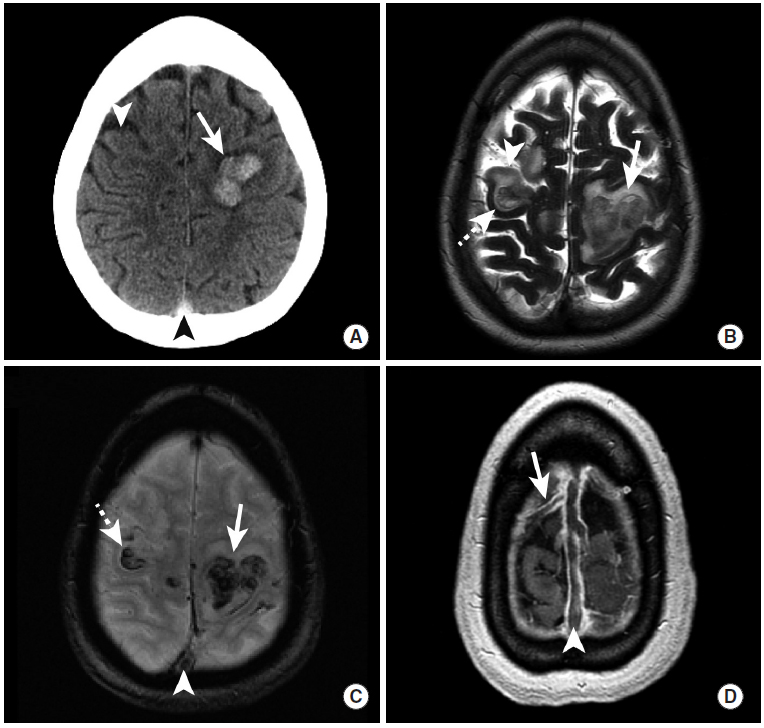

图15

高凝状态的女性患者,脑实质内出血继发于上矢状窦血栓形成。

CT平扫显示多发脑实质内出血灶(图A),MRI(图B~D)则进一步显示了脑实质的低信号出血灶,病灶周围并伴有周围高信号的水肿。在图C和图D中,上矢状窦内的充盈缺损(三角箭头)为血栓,即患者发生颅内出血的原因。图D中还可见延伸至右前皮质静脉中的充盈缺损。